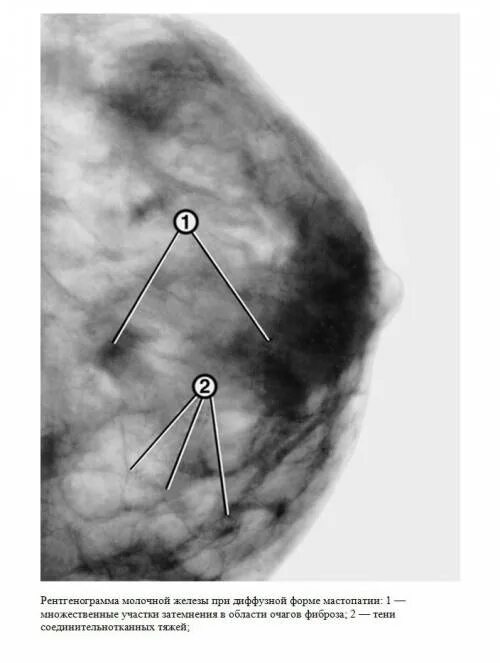

Диффузно фиброзный компонент